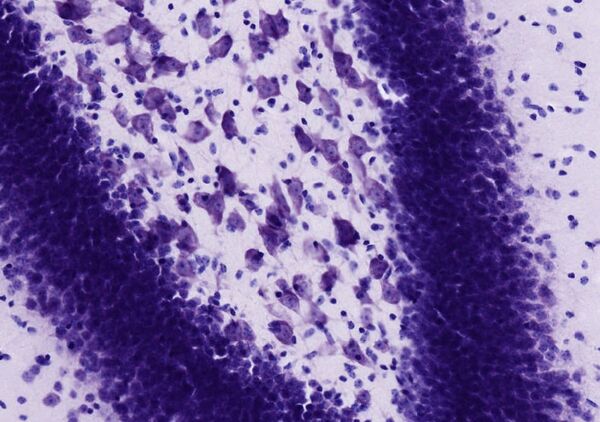

Вещество Ниссля (базофильное вещество Ниссля, хроматофильное вещество Ниссля, тигроидное вещество, тигроид) — скопления уплощённых цистерн гранулярной эндоплазматической сети[1], выявляемые в нейроне с помощью метода окраски по Нисслю.

Долгое время базофильное вещество Ниссля рассматривалось как таинственная материальная субстанция, неким образом определяющая свойства нервных клеток. Однако, впоследствии с помощью электронной микроскопии выяснилось, что базофильное вещество — не что иное, как скопление уплощённых цистерн гранулярной эндоплазматической сети, расположенных параллельно друг другу, которые при окрашивании специальными красителями выявляются в виде базофильных зёрен или глыбок.

Базофильные глыбки локализуются в перикарионе и дендритах, но никогда не обнаруживаются в нейритах и их конусовидных основаниях (аксонных холмиках)[1]. Большое содержание рибонуклеопротеидов и белково-полисахаридных комплексов в базофильных глыбках свидетельствуют о интенсивно происходящих в нейронах процессах синтеза нейросекреторных белков, интегральных белков плазмолеммы и белков лизосом[2], обеспечивающих поддержание массы перикарионов, отростков и их синаптической функции. Базофилия обусловлена большим количеством РНК в составе рибосом[1].